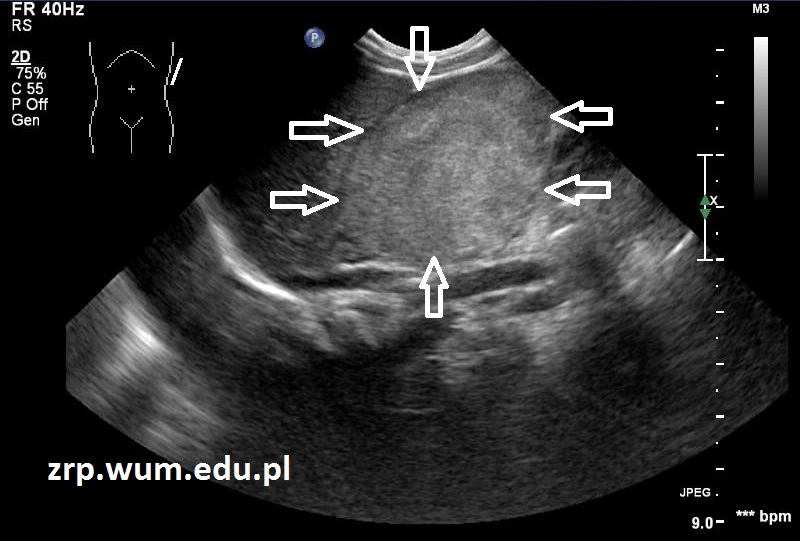

Przypadek 32: Dziewczynka w 1. dobie życia, w badaniu USG po urodzeniu stwierdzono guz wywodzący się z nadnercza lewego oraz liczne ogniska meta w wątrobie.

Wątroba znacznie powiększona, w całości o nieprawidłowej strukturze, z bardzo licznymi zmianami ogniskowymi o charakterze meta.

(guz - białe strzałki; nadnercze – czarna strzałka; nerka – czerwona strzałka; meta w wątrobie - kilka zmian oznaczono pomarańczowymi strzałkami).